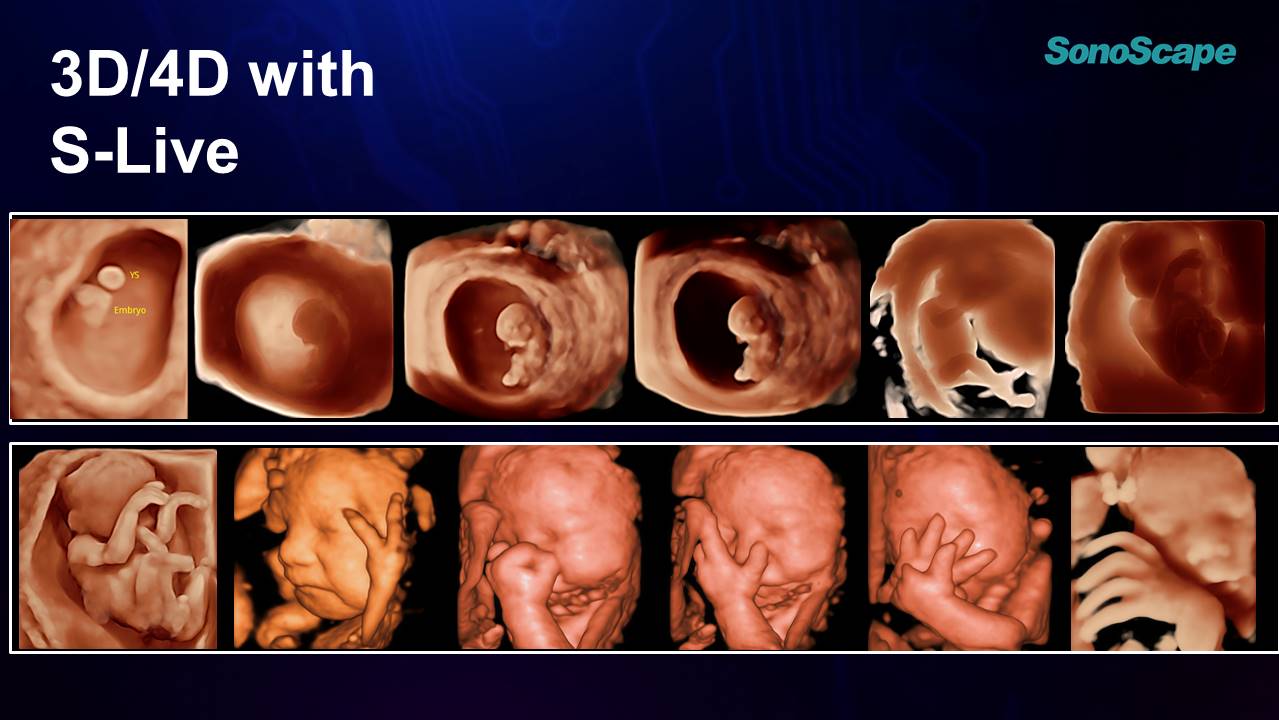

HD PORTRE

Derin öğrenme teknolojisine dayalı ,büyük veri yüz özelliklerinin uygulanması ile HD Portre , Cilt dokusu ve saç işleme yeteneklerini geliştirerek , fetal cilt görünümünü ve yüz özelliklerini ön plana çıkarır.